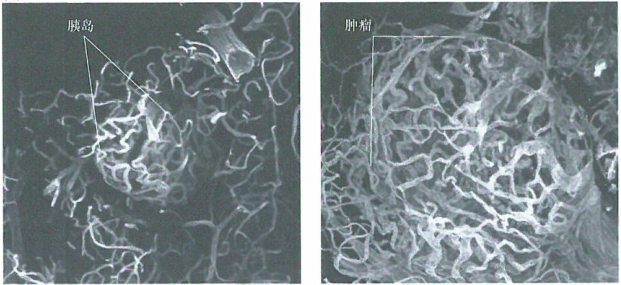

Kit作为干细胞因子(SCF)的受体是一个重要的生长因子,可触发特定亚系的造血前体细胞的生长。小鼠的一个缺陷是缺乏形成肥大细胞的能力。在缺乏Kit受体的Rip-Tag小鼠中,胰岛细胞瘤以在标准的Rip-Tag小鼠中观察到的常规速度始动。然而,这些肿瘤不能生成血管,并且这些小的增生物的细胞增殖速率被相等速度的凋亡所补偿。因此,这些肿瘤大小保持在一个的尺度上(直後0.1~0.2mm)。

出国看病机构爱诺美康了解到,如果给这些小鼠移植含有野生型造血前体细胞的骨髓,可以弥补其肥大细胞的缺陷,启动胰岛中的血管生成,胰岛中的肿瘤细胞不再通过凋亡丢失,随后大的、致命的肿瘤很快就出现了。这证明驱动血管生成的能力依赖至少一种肿瘤相关间质的非内皮细胞成分(即来源于骨髓的肥大细胞)的作用。这些肥大细胞对血管生成开关的主要贡献似乎在于释放MMP-9,继而动员潜伏的VEGF并由此导致血管生成。但是,其他一些工作表明巨噬细胞同样参与肿瘤的血管形成。